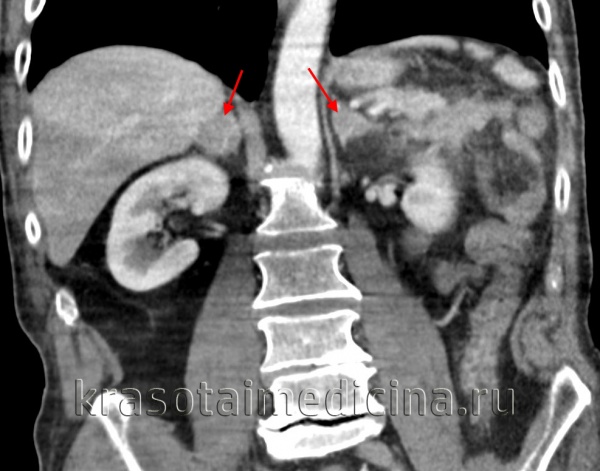

Диагностику надпочечниковой недостаточности начинают с оценки анамнеза, жалоб, физикальных данных, выяснения причины гипокортицизма. Проводят УЗИ надпочечников. О первичной надпочечниковой недостаточности туберкулезного генеза свидетельствует наличие кальцинатов или очагов туберкулеза в надпочечниках; при аутоиммунной природе гипокортицизма в крови присутствуют аутоантитела к надпочечниковому антигену21-гидроксилазе. Дополнительно для выявления причин первичной надпочечниковой недостаточности может потребоваться МРТ или КТ надпочечников. С целью установления причин вторичной недостаточности коры надпочечник КТ и МРТ головного мозга.

- КТ надпочечников. Рентгенологическая визуализация рекомендована для обнаружения кровоизлияний, очагов дистрофии и других патологических признаков, которыми проявляется первичная надпочечниковая недостаточность. Для оценки структуры гипофиза показана рентгенография турецкого седла, КТ головного мозга.